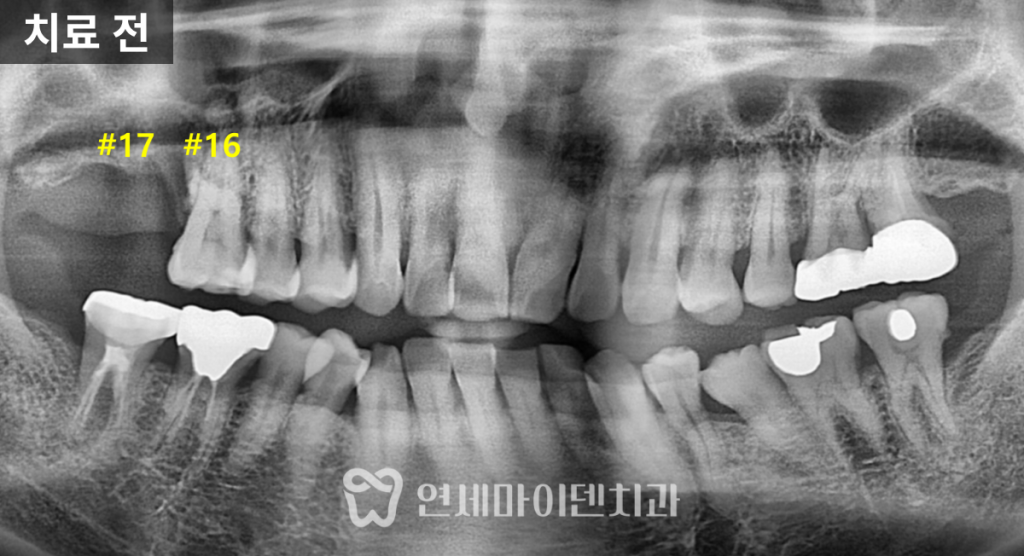

검사 결과,

17번 치아는 뼈 높이가 전반적으로 낮았고

상악동 점막이 두꺼워진 상태였습니다.반면 16번 치아는

깨지고 염증이 있었지만

정밀 평가 결과

충분히 살려볼 수 있는 여지가 있었습니다.이에 따라 치료 계획은 다음과 같이 세웠습니다.

- 16번 치아: 신경치료 및 잇몸치료를 통한 보존

- 17번 치아: 상악동 거상술을 동반한 임플란트 식립